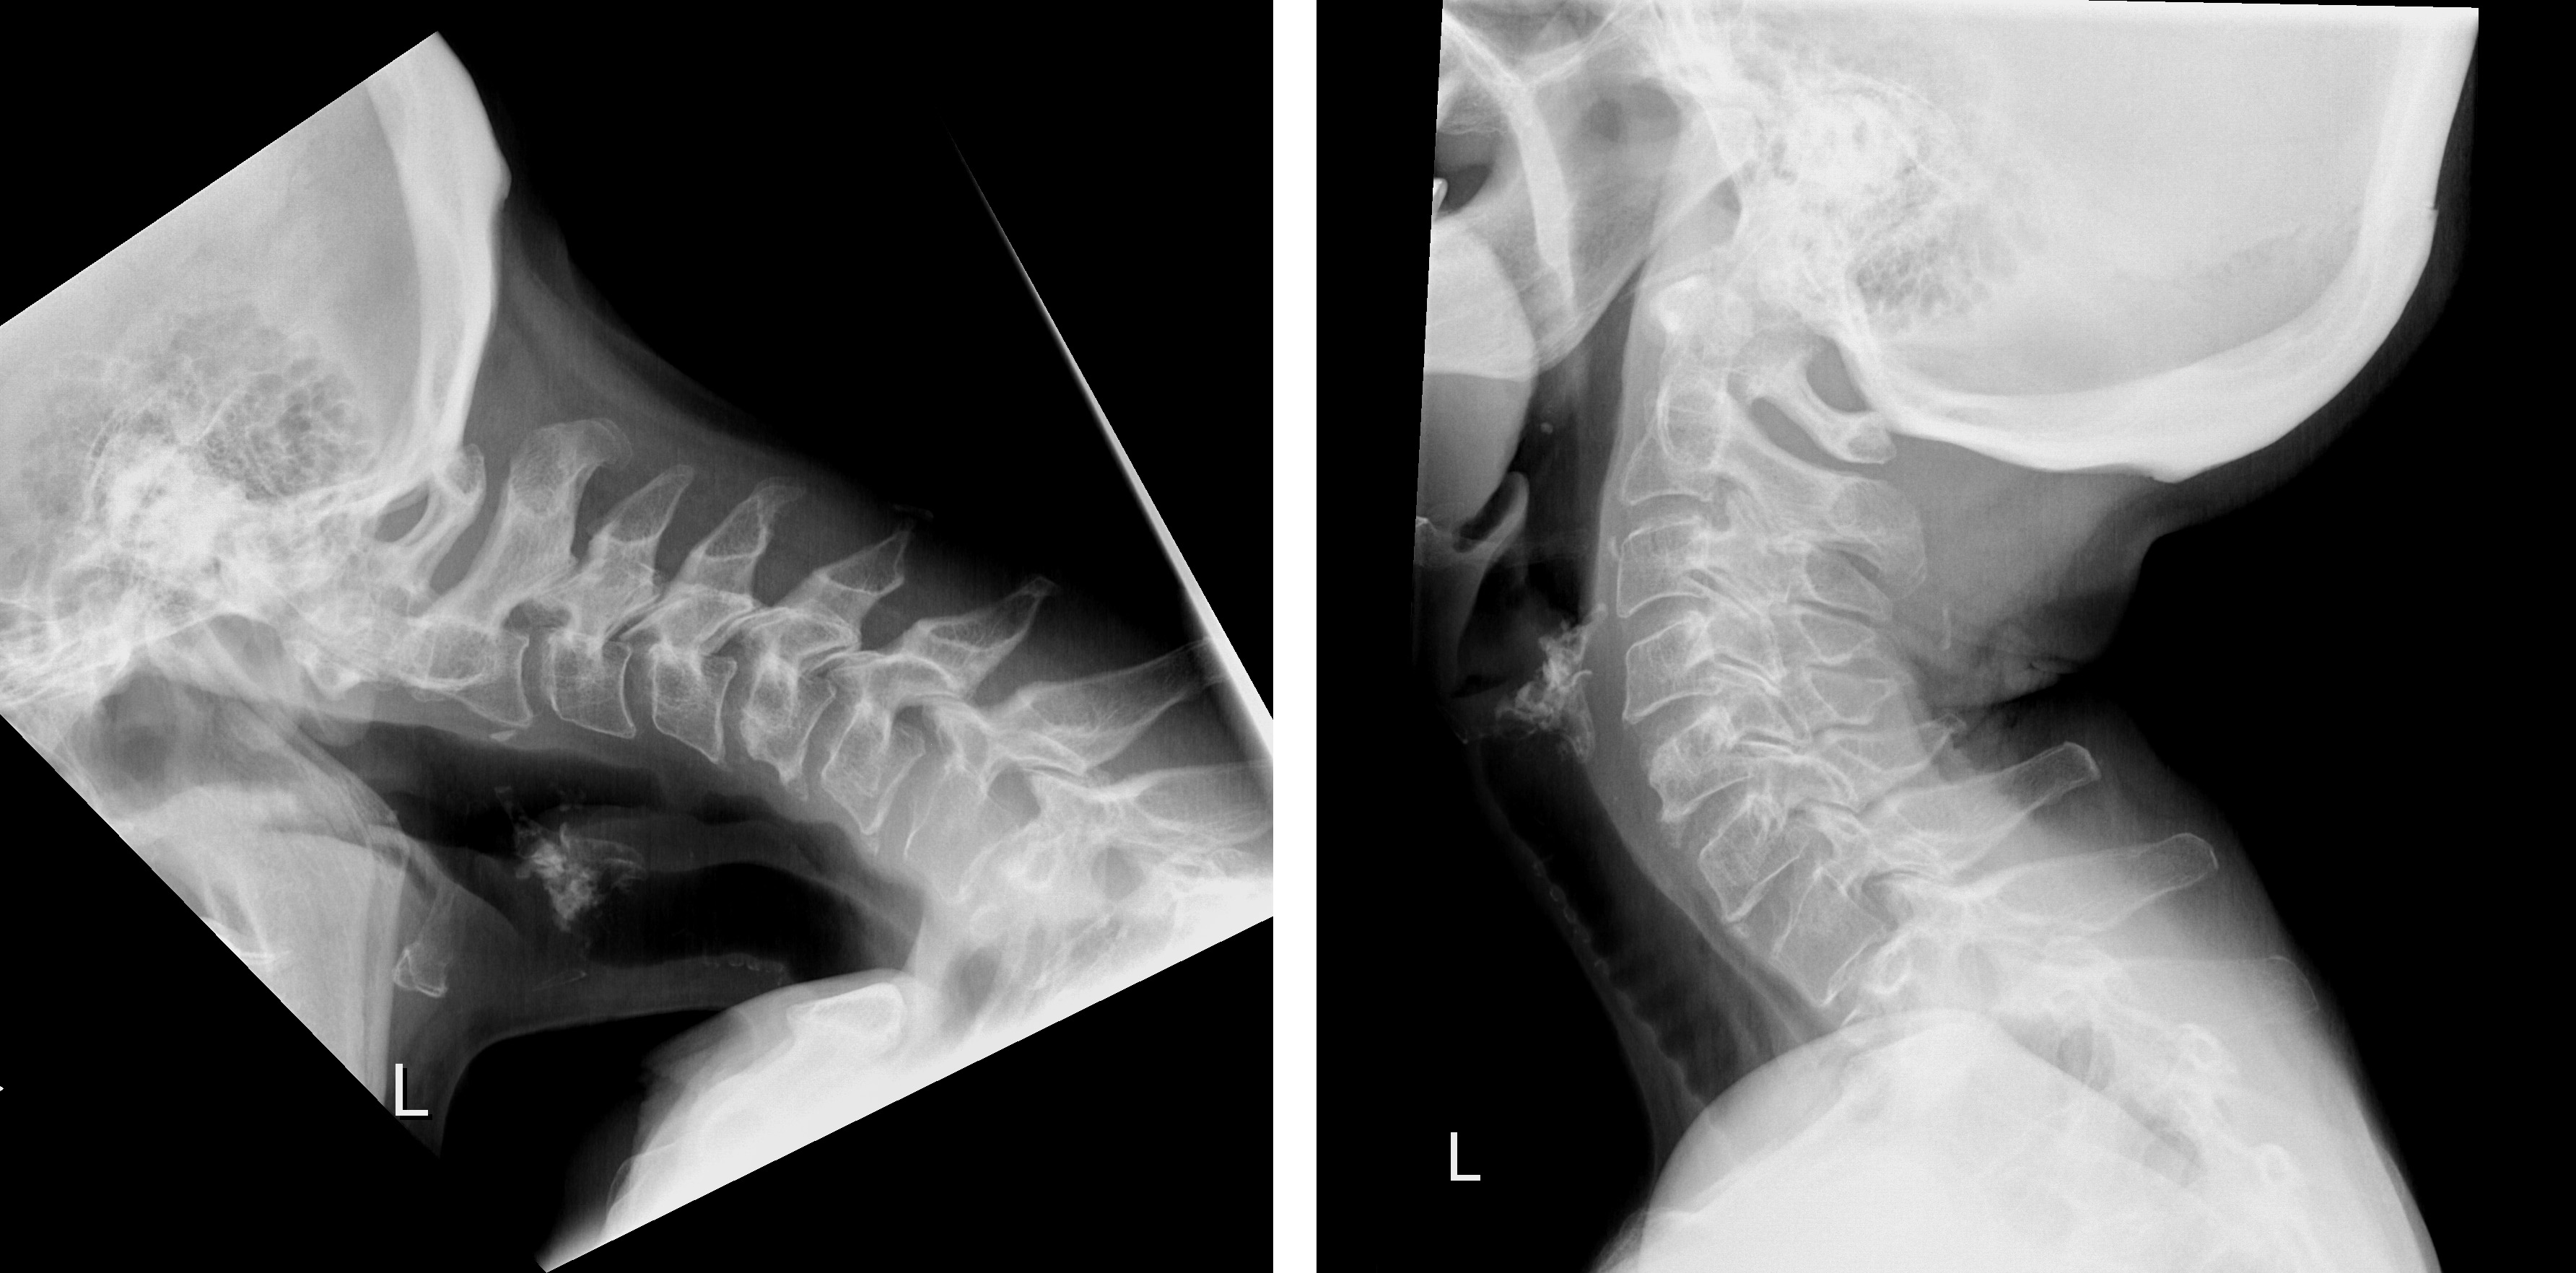

Dropped head syndrome (DHS), also known as floppy head syndrome, is a rare condition with a broad differential diagnosis. DHS has a considerable impact on the health and qual-ity of life of affected individuals. The neck extensors are weakened to such an extent that patients are unable to hold the head erect. Until now, extensive fixation and fusion of the cervical and thoracic spine has been the only possible treatment for DHS.

Prof. Mazda Farshad, Surgeon in Chief and Director of the University Spine Center Zurich at Balgrist University Hospital, and his team have now developed a new surgical technique making it possible to treat DHS for the first time successfully without fusion. This tech-nique, known as «occipitopexy», supports the head by using ligaments attached to the spine. Today, eighteen months after surgery, the patient, a 68-year-old female, is not only still able to support and maintain a normal head position, but also perform head movement functionality. This represents a less radical and very promising treatment to relieve the pa-tients’ suffering without restricting their quality of life by spinal fusion.